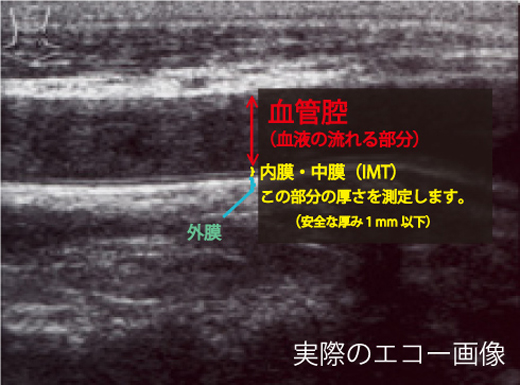

血管エコーパーフェクトガイド―動脈硬化の早期発見 (循環器臨床, 血管年齢・頸部エコー・動脈硬化について | 名古屋市昭和区 横山,

血管年齢・頸部エコー・動脈硬化について | 名古屋市昭和区 横山, ストップ!動脈硬化「危険を予測 最新検査」 - きょうの健康 - NHK,

ストップ!動脈硬化「危険を予測 最新検査」 - きょうの健康 - NHK, 循環器検査 | 名古屋循環器科・内科 | 中村区名駅,

循環器検査 | 名古屋循環器科・内科 | 中村区名駅, 頸動脈エコーと動脈硬化検査 | 川崎市幸区の川崎中央クリニック,

頸動脈エコーと動脈硬化検査 | 川崎市幸区の川崎中央クリニック, 血管年齢 - 高津駅前はら内科ハートクリニック,

血管年齢 - 高津駅前はら内科ハートクリニック, 動脈硬化③ - 頚動脈超音波(頚部US)検査 - | 2020年 | コラム,

動脈硬化③ - 頚動脈超音波(頚部US)検査 - | 2020年 | コラム, 四谷三丁目・四谷・四ツ谷の内科・循環器内科・外科 | まがり,